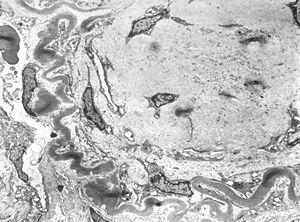

F,14y. | Alport syndrome - split and laminated, thick/thin basement membranes